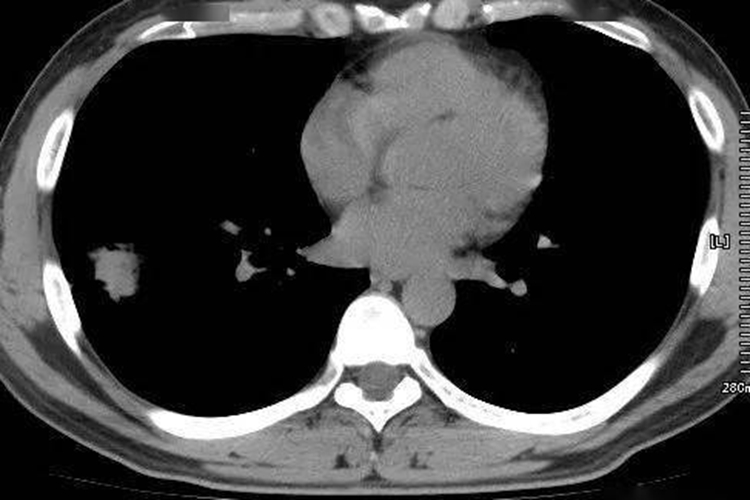

肺癌又称原发性支气管肺癌,临床常见咳嗽、血痰、胸痛、发热、气促等症状。影像学表现可分为中央型肺癌和周围型肺癌两种,具体如下:

中央型肺癌:发生在肺段和段以上支气管,表现为病变处支气管壁增厚、支气管腔狭窄;肺门出现形态不规则的软组织肿块;远端肺组织阻塞性改变,包括阻塞性肺炎、肺不张,表现为远端肺组织实变,或肺叶、肺段均匀性密度增高,伴肺纹理聚拢、体积缩小或右肺上叶不张时,下缘形成反“S”征。